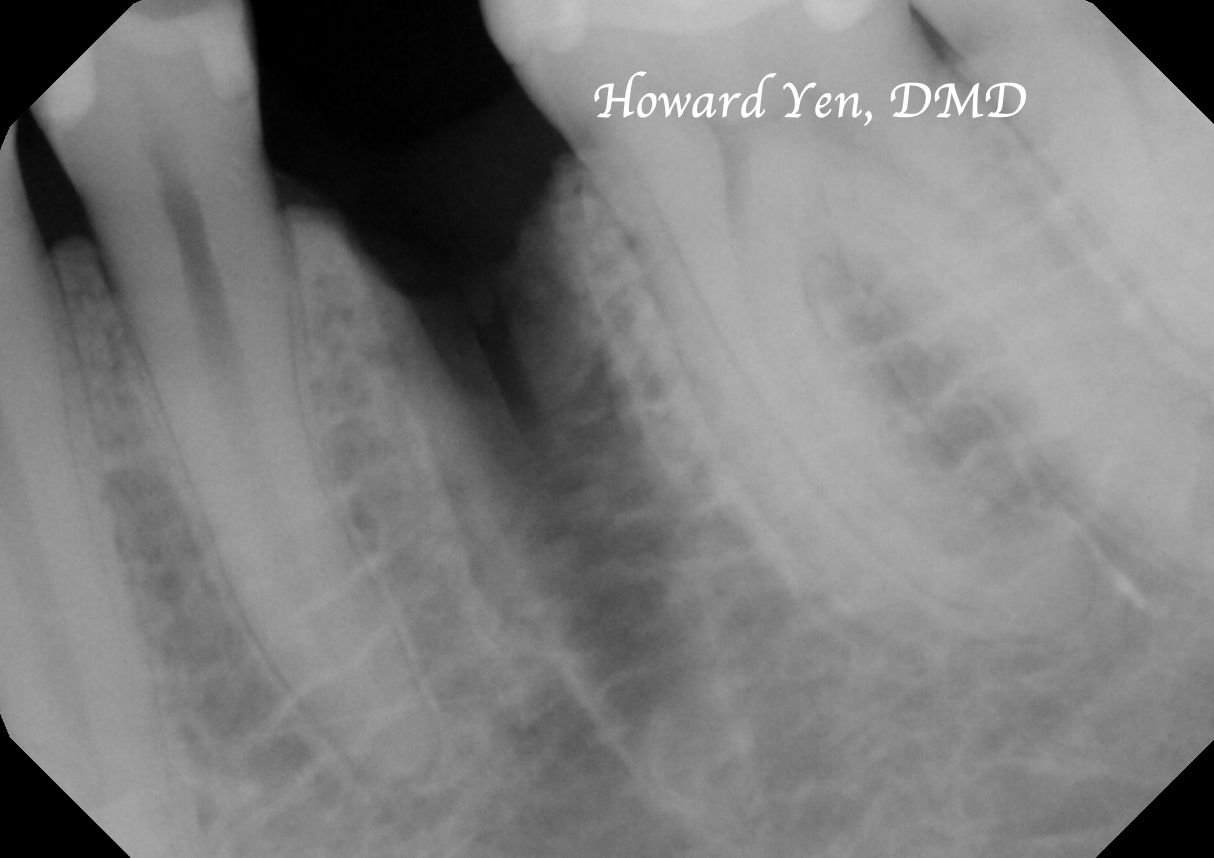

Once a natural tooth is removed from jaw bone, the jaw bone will undergo resorption (shrinkage) in volume. When there is a plan to replace the extracted tooth with dental implant, then there’s some treatment strategies to help reduce the rate of jaw bone shrinkage in order to provide adequate bone volume to receive dental implant. This procedure is often NOT necessary if there’s no plans to replace the tooth nor a strategic value (such as wisdom tooth extractions, the furthest molar in the mouth).